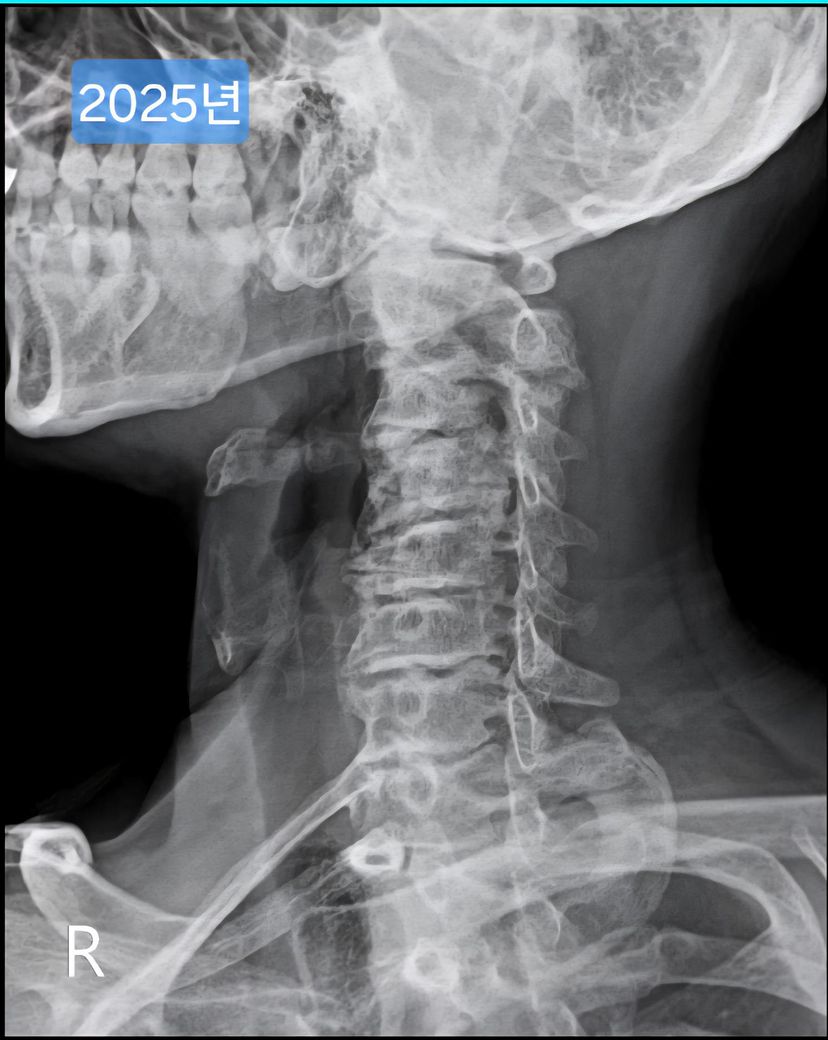

목이 경추사이가 좁고, 일자목인데 헬스를 해도 될까요?

선생님이 같이 찍힌 목사진을 보시더니 심각하다며..경추사이 간격도 좁고, 일자목이고..

며칠전 찍은 2025년도 엑스레이와 9년전 사진을 업로드 해 드리겠습니다.

(이미지에 좌측상단에 해당연도 표시했습니다.)

• 1번 째 사진

• 2번 째 사진